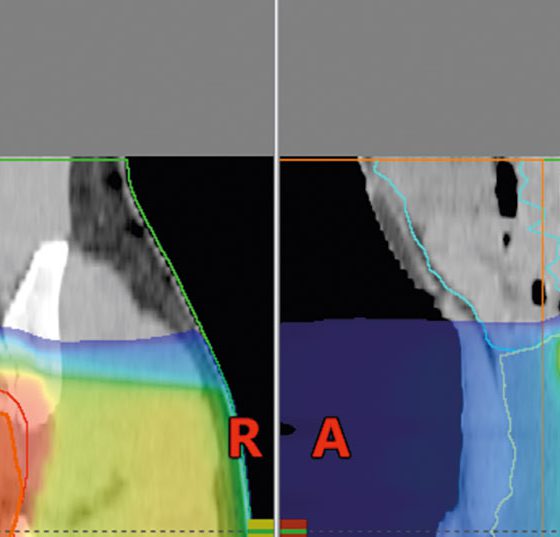

• Von der adjuvanten zur neoadjuvanten Radio-/Radiochemotherapie

Multimodale Therapie des Rektumkarzinoms

Analog zur S3-Leitlinie der DKG 2014 können stadiumabhängig Empfehlungen getroffen werden. Stadium I: Hier ist die alleinige totale mesorektale Exzision (TME) Standard. Stadium II und III: Die präoperative Radio(chemo)therapie ist...…